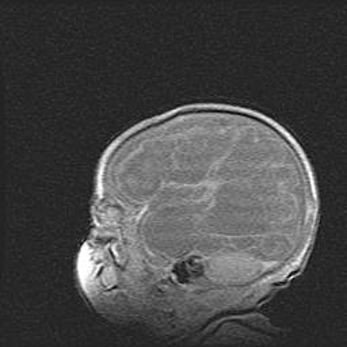

Неполная лизэнцефалия (пахигирия). Открытая гидроцефалия.

Возраст: 17 дней

Вес: 3110 г

Пол: мужской

Окружность головы: 33,5 см

Срок гестации: 35-36 недель

Лизэнцефалия—недоразвитие корковой пластинки и мозговых извилин в результате нарушения миграции нейронов коры. Поверхность мозговых полушарий гладкая. Микроскопически выявляется отсутствие нормальных слоев коры и скопление групп нейронов в подкорковом белом веществе.

Пахигирия—уменьшение числа вторичных извилин. В пораженном полушарии нервные клетки образуют толстый недифференцированный слой с неправильно расположенными нервными волокнами и группами гетеротопных клеток. Нервные клетки незрелые. Белое вещество истончено. При этом нередко аномально развит корково-спинномозговой путь.